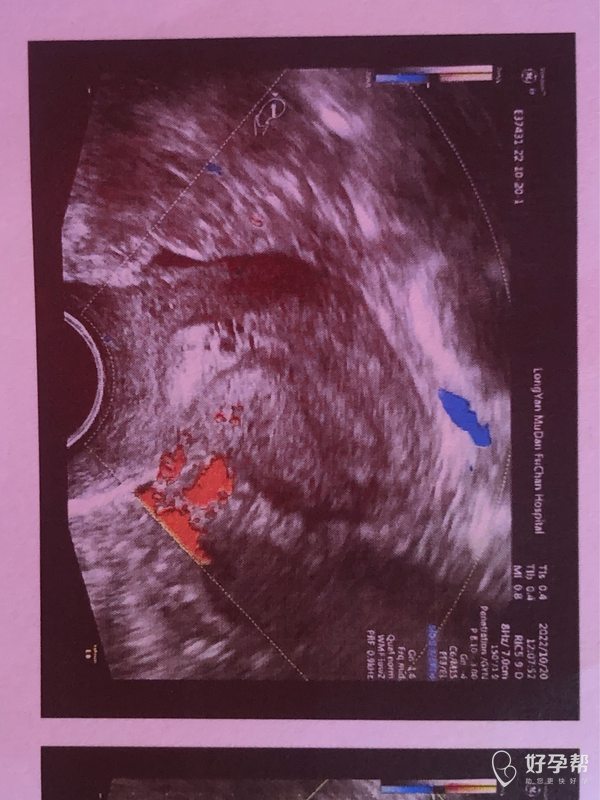

医生好这是我月经第8天的阴道彩超图请问按图上

可以继续观察子宫内膜厚度、形态、血流等。月经第8天,时间短,建议继续监测子宫情况。